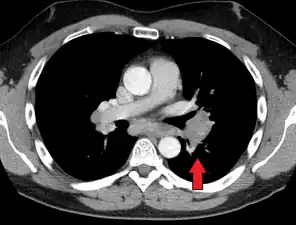

CT scan of the chest showing lymphadenopathy (arrows) in the mediastinum due to sarcoidosis

Diagnosis of sarcoidosis is a matter of exclusion, as there is no specific test for the condition. To exclude sarcoidosis in a case presenting with pulmonary symptoms might involve a chest radiograph, CT scan of chest, PET scan, CT-guided biopsy, mediastinoscopy, open lung biopsy, bronchoscopy with biopsy, endobronchial ultrasound, and endoscopic ultrasound with fine-needle aspiration of mediastinal lymph nodes (EBUS FNA). Tissue from biopsy of lymph nodes is subjected to both flow cytometry to rule out cancer and special stains (acid fast bacilli stain and Gömöri methenamine silver stain) to rule out microorganisms and fungi.[100][101][12][102]